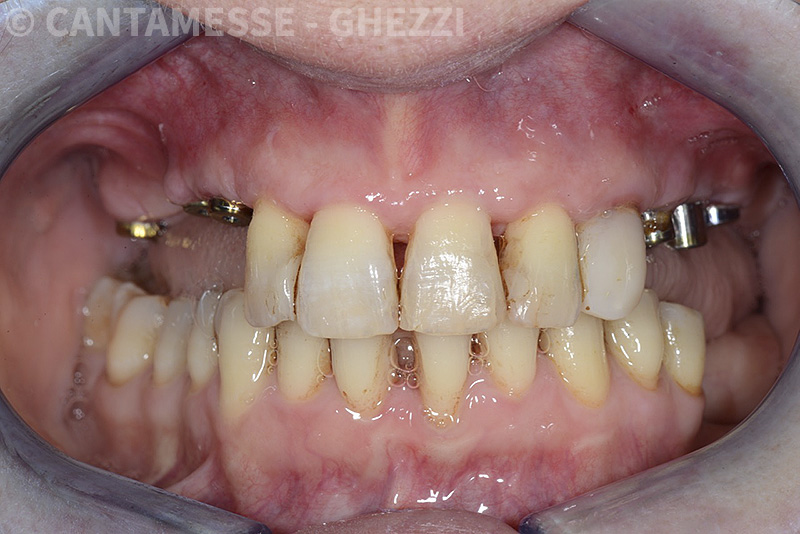

PREMESSA: in seguito all’estrazione dell’incisivo laterale superiore di destra, resasi necessaria per cause batteriche, si decide di affrontare il caso con il posizionamento di un impianto in sostituzione dell’elemento mancante dopo guarigione del sito infetto. Con tecniche rigenerative sia dei tessuti ossei mancanti a causa dell’infezione pregressa, sia dei tessuti gengivali che appaiono inizialmente troppo spostati in alto, si ripristina una corretta morfologia delle parabole (contorni) gengivali e delle papille interdentali (triangoli di gengiva tra due denti vicini).

Vengono utilizzati 2 tipi di provvisori: il primo, cementato ai denti vicini, viene utilizzato dal momento dell’estrazione del dente fino ad impianto osteointegrato (circa 6 mesi); il secondo, avvitato direttamente all’impianto, ha una funzione di prova estetica ma soprattutto di guida per la maturazione dei tessuti gengivali peri-implantari portandoli verso la maturazione completa prima di posizionare la corona finale in disilicato di litio.